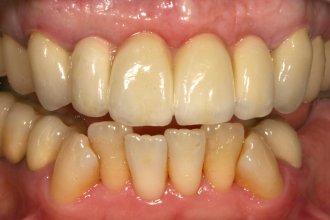

Fotos zur Farbbestimmung, Gesichtsanalyse und Korrekturhilfe